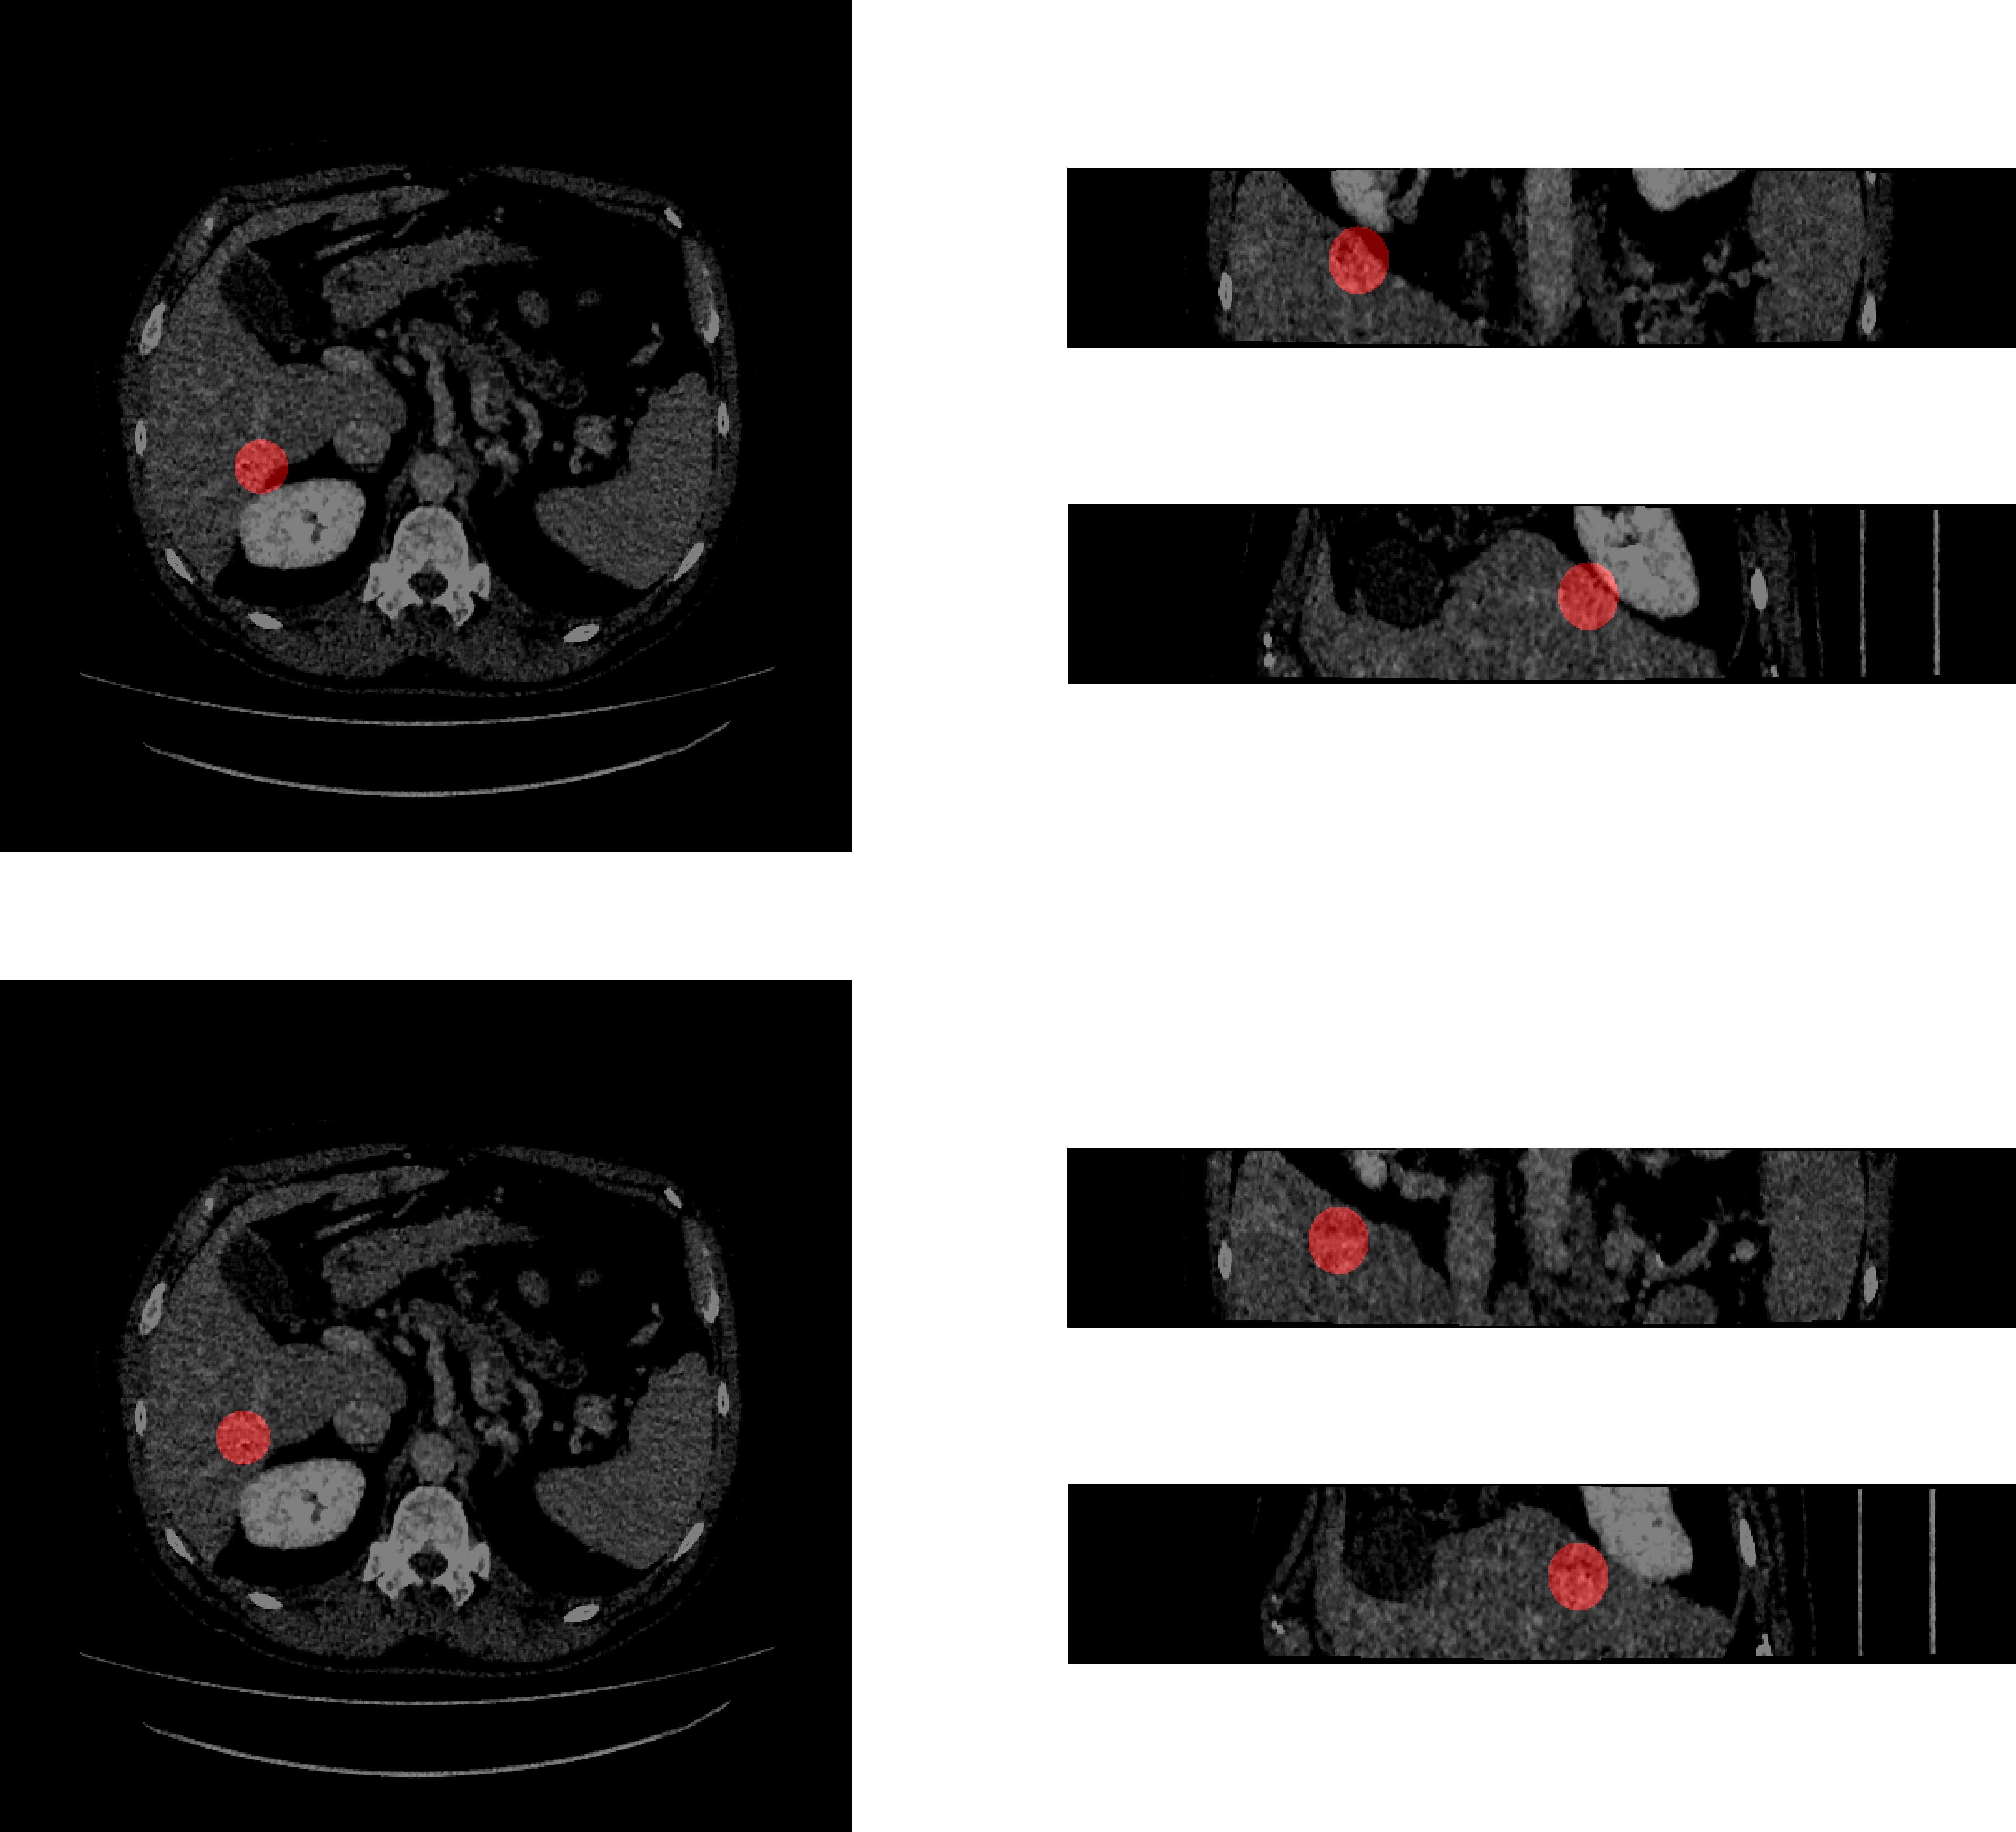

Some initial placements for the ROIs were such that they were not fully enclosed within the liver. To resolve this issue, the flawed ROIs were shifted such that they were fully encapsulated within the ROI. Each shift was a maximum of 3 cm along any axis. An example of a flawed ROI and the post-shift ROI is presented in Figure 2.

Refer to caption

Figure 2: Example flawed ROI (above) and the ROI post-shift (below) (left: axial view, upper right: coronal view, lower right: sagittal view).